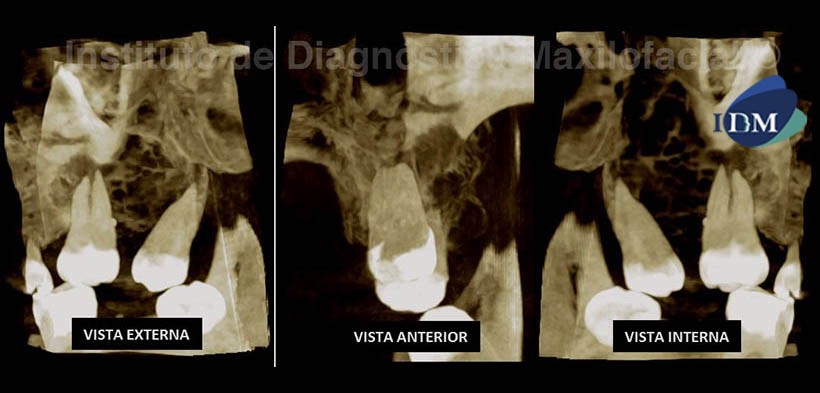

Al estudio con tomografía volumétrica, en la reconstrucción panorámica (Fig. 2) confirmamos la presencia de una masa isodensa en el hueso alveolar, ocupando parcialmente el seno maxilar del lado izquierdo y condicionando una probable comunicación bucosinusal; observando, en la zona correspondiente al reborde alveolar de la pieza 2.7, un trabeculado muy fino e irregular dentro de la lesión.

En los cortes coronal, sagital y axial (Fig. 3); notamos la presencia de una lesión tumoral localmente agresiva y multilocular, con una configuración interna conformada por finas trabéculas entrelazadas entre si y localizada en el reborde alveolar de la pieza 2.6, extendiéndose hasta la tuberosidad, condicionando el desplazamiento de la pieza 2.8; además se observa la expansión de la tabla ósea palatina y, en mayor grado, la expansión de forma irregular de la tabla ósea vestibular condicionando su erosión y, probablemente, causando la invasión del tejido tumoral hacia la cavidad oral. Así mismo condiciona el desplazamiento cefálico del piso del seno maxilar causando el ocupamiento parcial de este. Se consideran imágenes sugerentes de una lesión tumoral de origen odontogénico compatible con Mixoma.

En la reconstrucción 3D (Fig. 4), en proyección de máxima intensidad (MIP), se aprecia la configuración interna del tumor, compuesto por trabeculas finas y otras más gruesas, formando lóculos redondeados y de menor tamaño asemejando un aspecto de panal de abeja. A la vez se puede observar la expansión de la cortical ósea vestibular, presentando un aspecto irregular. El resultado anatomopatológico fue Mixoma Odontogénico.

Como hallazgo imagenológico, nótese la presencia de una perla del esmalte a nivel del tercio medio de la raíz distal de la pieza 2.6.